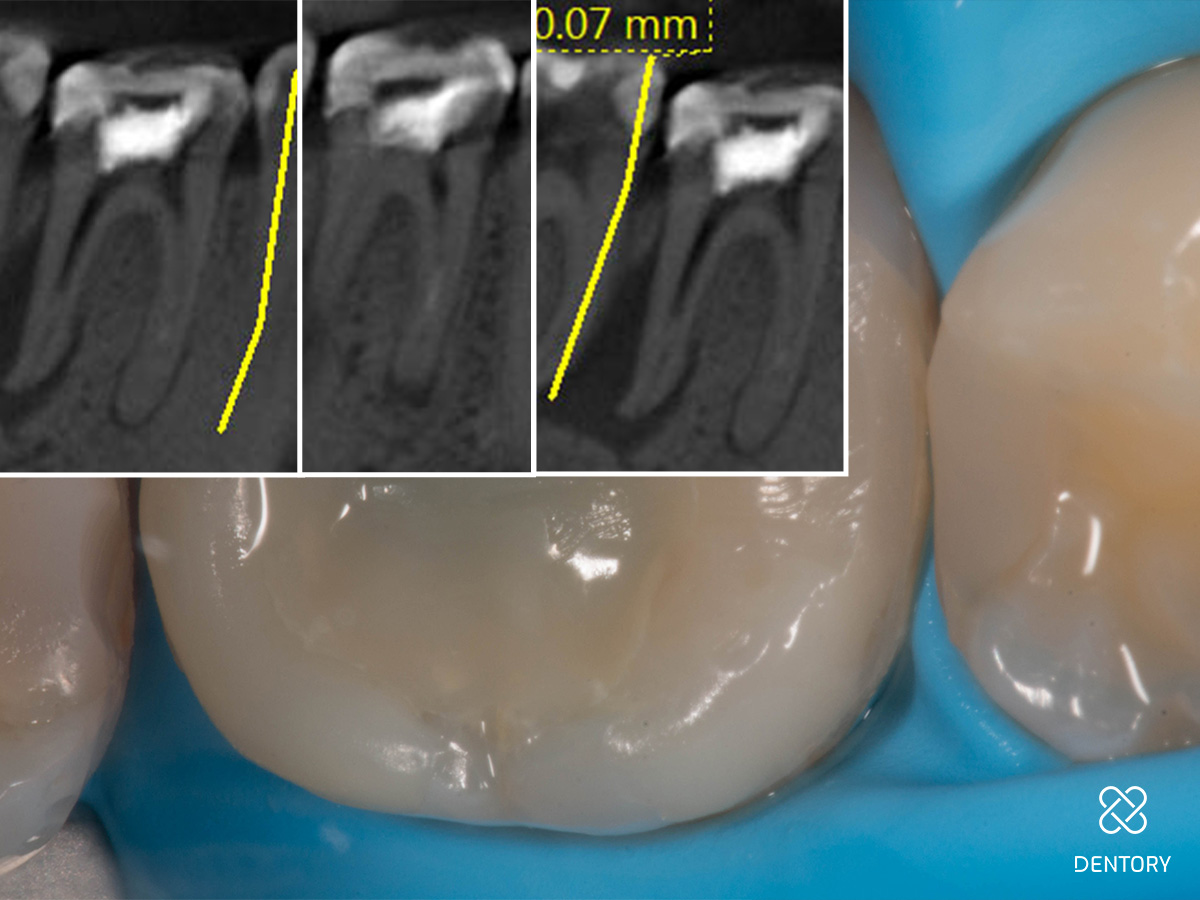

Abbildung 1

Ausgangssituation: Das initiale Röntgenbild zeigt den Grund für die Schwellung.